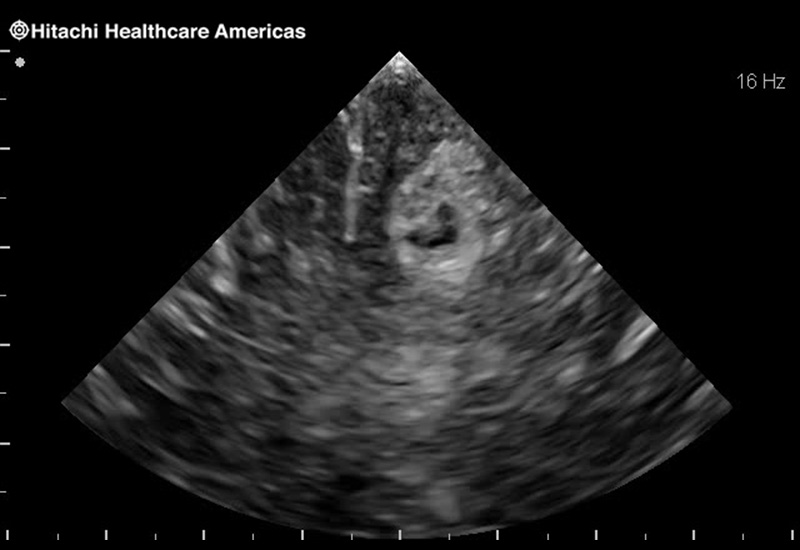

Superior guidance for all applications

Fujifilm Healthcare Americas is committed to designing tools that help surgeons navigate inside the human body and provide the necessary information to immediately make critical surgical decisions.

Fujifilm Healthcare's dedication to Surgeons provides outstanding ultrasound technology, professional support and the specialized tools necessary to best perform comprehensive real-time ultrasound imaging in Breast Surgery, General Surgery, Laparoscopic Surgery, Neurosurgery, Robotic Surgery and Surgical Oncology.

The Arietta 65 has many advanced and unique probes that fully cover the expanding range of procedures that benefit from ultrasound guidance.

The Arietta 65 has many advanced and unique probes that fully cover the expanding range of procedures that benefit from ultrasound guidance.